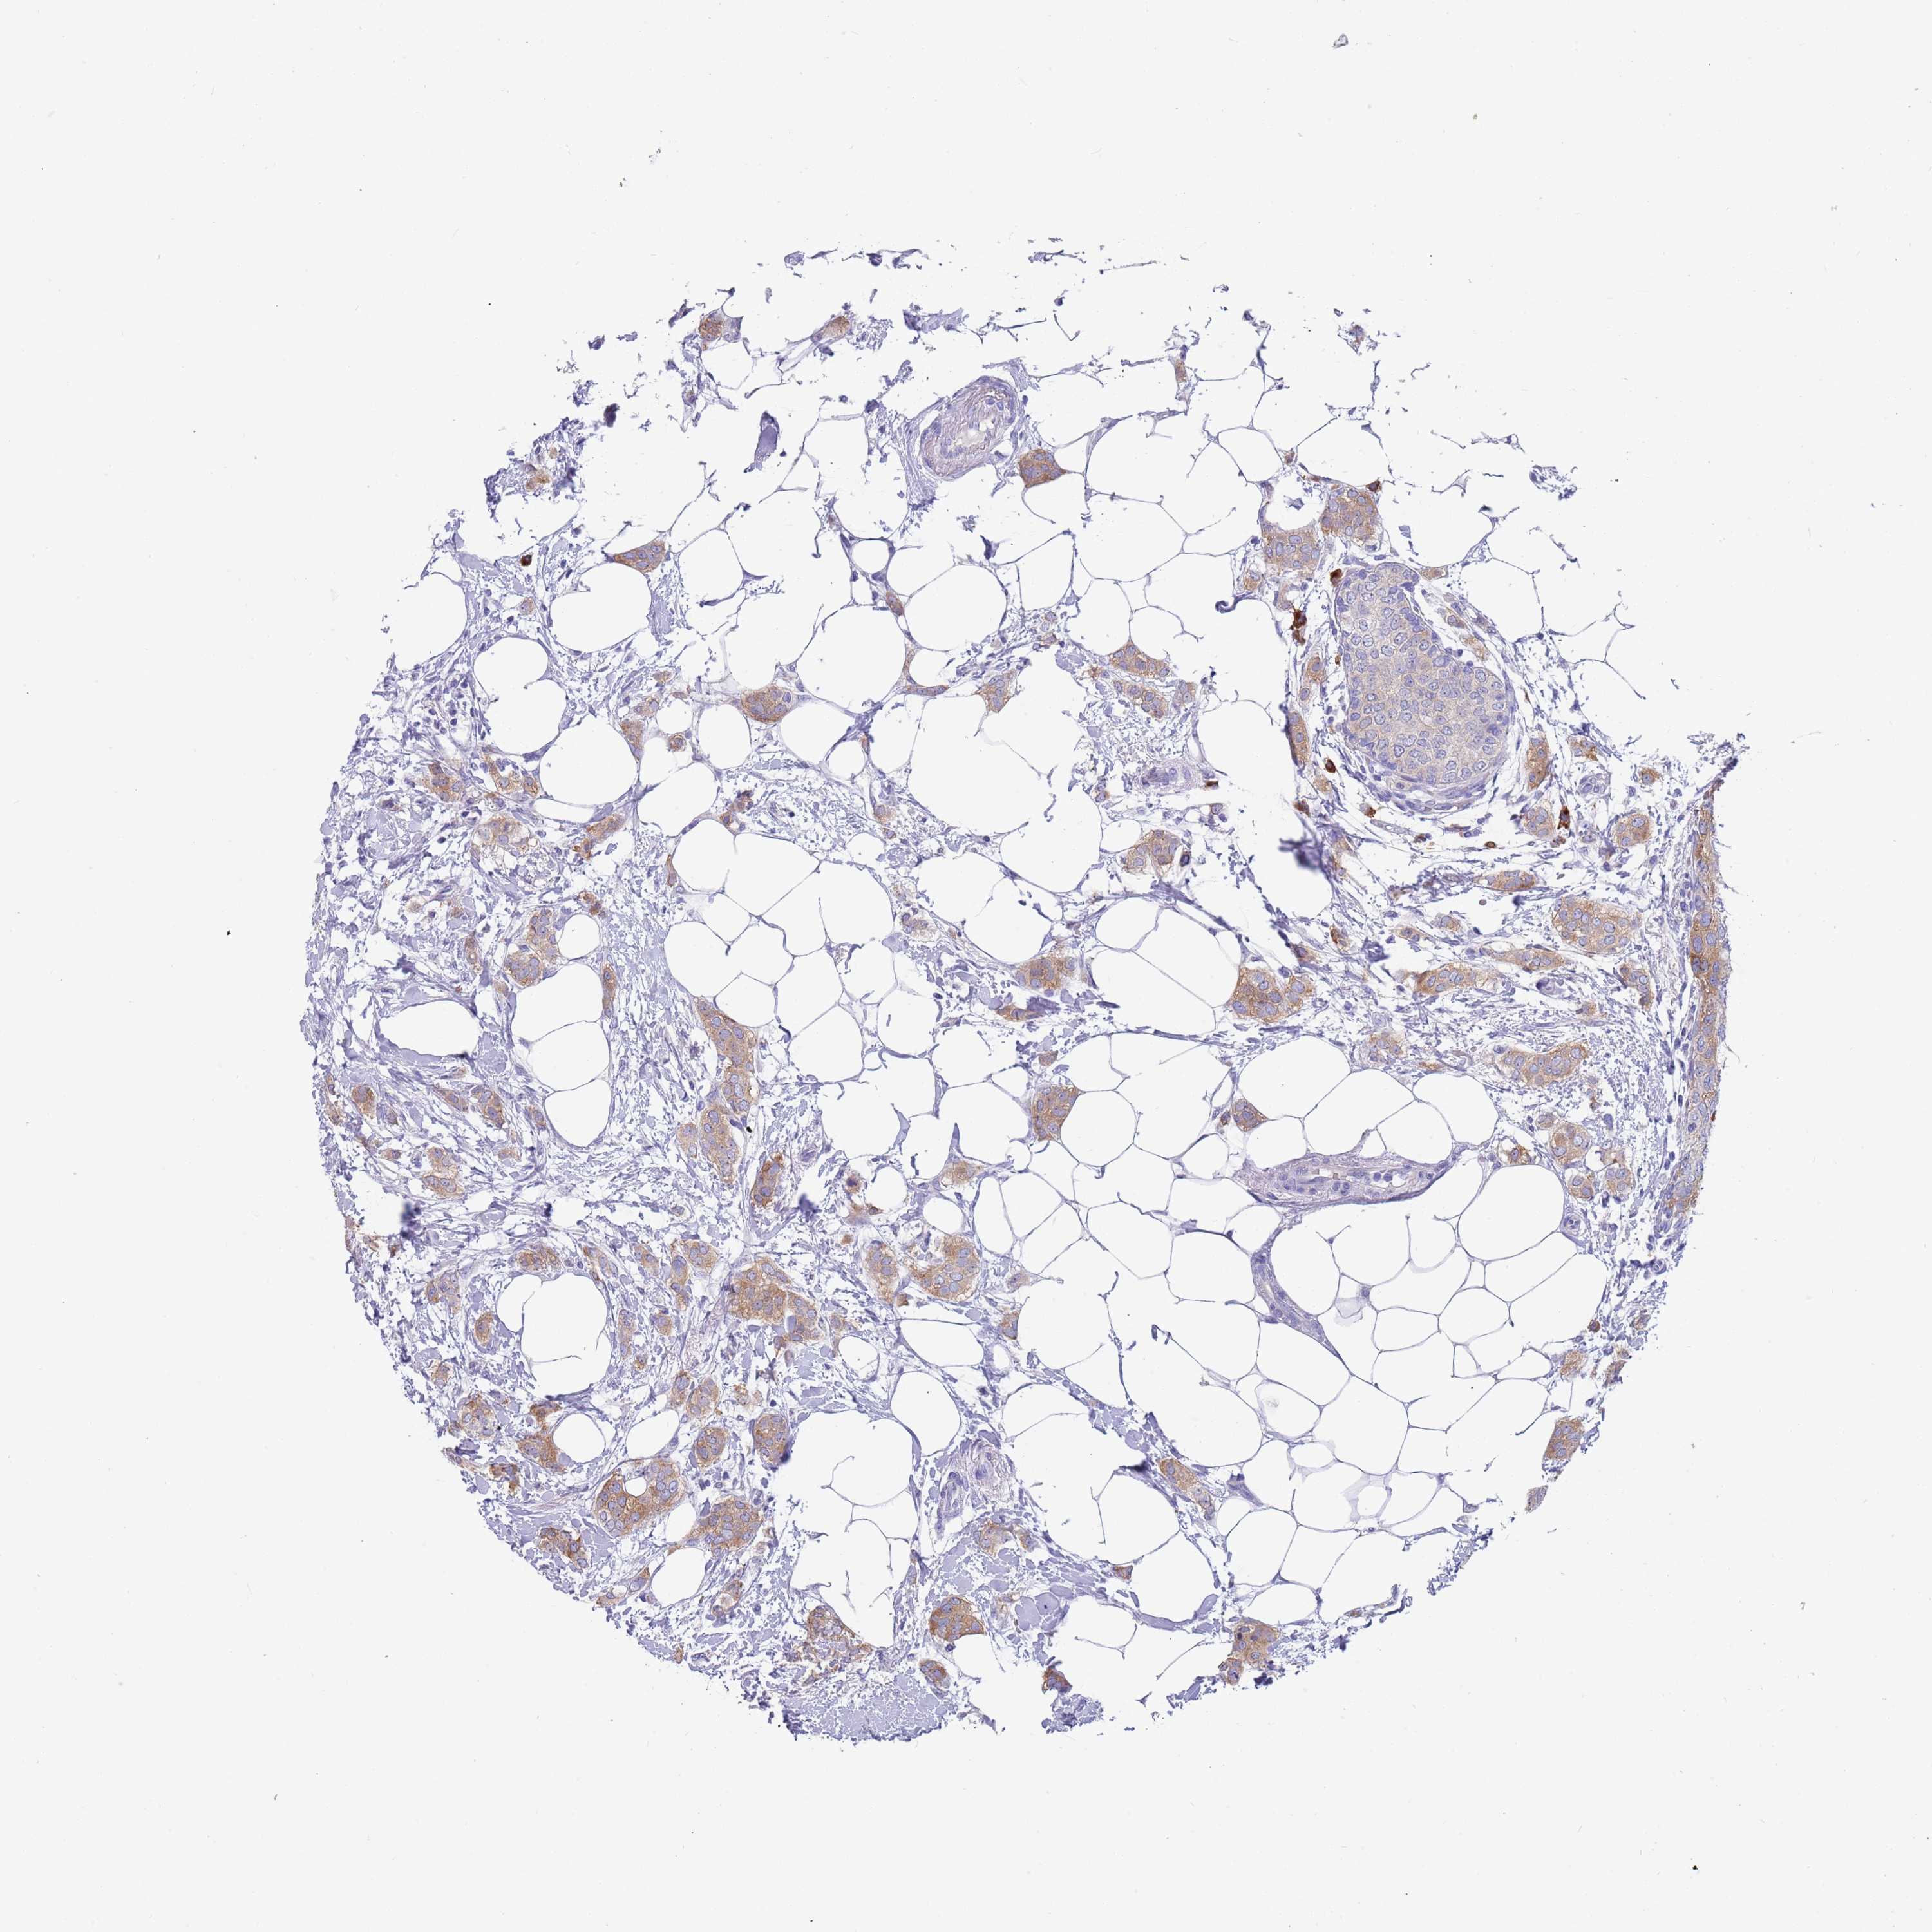

CANCER BREAST CANCER Show tissue menu

BRCA TCGA BRCA VALIDATION PROTEIN EXPRESSION